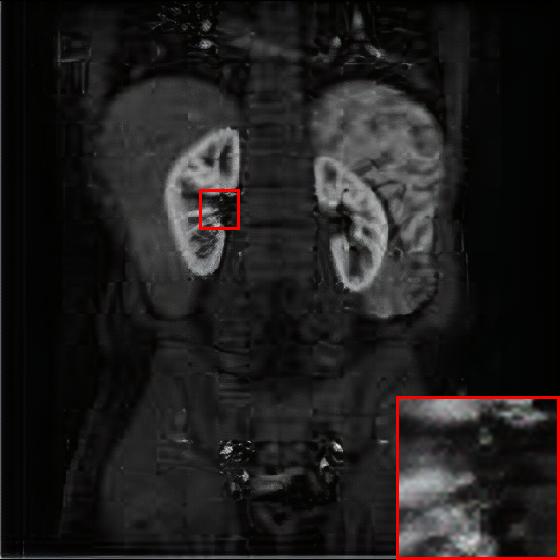

Figure 4: Reconstruction results of each algorithm for abdominal MRI images.

The PNSR/SSIM test results for the knee MRI test images for all contrast methods are shown in Table 1. The PNSR/SSIM test results for the abdominal MRI images are shown in Table 2. It’s worth noting that all metrics were calculated on cropped photos in order to eliminate the impact of non-subject areas. The quantitative results show that for knee MRI images, our proposed TT\mathrm{T}-GAN model achieves the best performance on the PSNR/SSIM metrics. For abdominal MRI images, our model essentially achieves optimal performance, with individual image WDSR slightly outperforming our model. The experimental results cousin that our model is more suitable for medical image super-resolution reconstruction than the existing deep learning-based image super-segmentation models.

We likewise give the visualization comparison results for each comparison algorithm, as shown in Fig. 3 and Fig. 4. It can be seen that the reconstructed images based on bicubic interpolation and deep learning based EDSR and WDSR both show oversmoothing phenomenon and some loss of detail information of the images. In contrast, our T-GAN performs better for the reconstruction of detail information due to the texture Transformer structure.